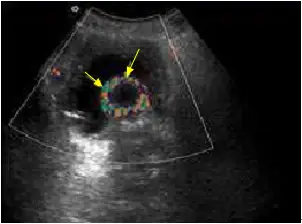

附圖為膀胱都卜勒超音波掃描,箭號所指最可能為何?

本影像為膀胱彩色都卜勒超音波掃描(color Doppler ultrasound),可見整體呈現扇形掃描視野。

- 影像中央可見一個圓形(球狀)結構,具有低回音至無回音(anechoic)中心,周圍有薄層強回音壁

- 此圓形結構周圍環繞著豐富的彩色都卜勒訊號,呈現混合色彩(紅色、藍色、綠色等),形成一圈「環形火焰(ring of fire)」的外觀

- 黃色箭號指向兩處相似的彩色訊號位置

- 此彩色訊號並非真實血流,而是導管球囊界面與超音波探頭之間產生的都卜勒偽像(Doppler artifact)

影像解讀: 此「環形火焰」都卜勒偽像是 Foley 導尿管氣球在彩色都卜勒超音波下的典型特徵性表現。球囊充水後形成光滑曲面,其球型界面造成超音波信號的多重反射與相位偏移,使都卜勒系統誤判為